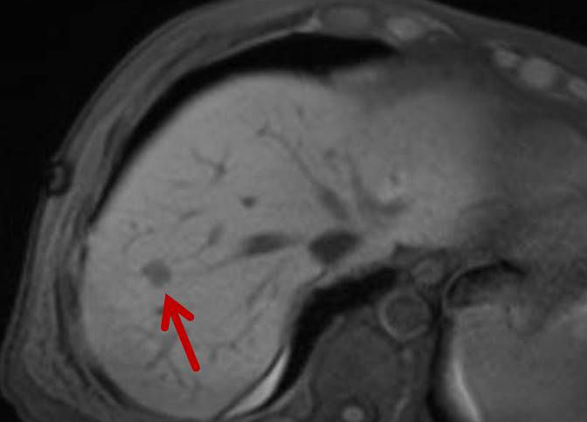

Thermoablation von Lebertumoren

Die minimalinvasive Thermoablation ist eine Therapieoption für Leberkarzinome und Lebermetastasen. Voraussetzung hierfür ist, dass bestimmte Bedingungen wie Tumorgröße, Anzahl und Lage des Zieltumors erfüllt sein. Ob ein Lebertumor mit einem thermoablativen Verfahren (Mikrowellenablation oder Radiofrequenzablation) sicher und effektiv behandelt werden kann, wird vor der Therapie interdisziplinär mit Kollegen aller für diese Fragestellung relevanter Fachrichtungen besprochen.